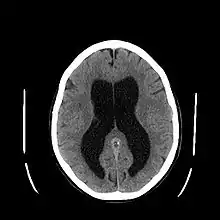

يعتمد التشخيص على التاريخ المرضي والفحص السريري، ومعرفة الحالة المصاحبة، بالإضافة إلى بعض الفحوصات الإشعاعية مثل :

- الأشعة المقطعية : وتعطي صور واضحة عن الحالة ومكان الانسداد.

إحدى الحالات المثيرة للاهتمام لمرضى اسستقاء الرأس كانت لرجل تقلص دماغه لورقة رقيقة من النسيج، وذلك بسبب تراكم السائل النخامي في جمجمته. أثناء طفولته أجربت له عملية وركبت له توصيلة، ولكن في سن الـ 14 تم إزالة هذه التوصيلة. في شهر 7 من عام 2007, في عمر 44 عام، ذهب إلى المشفى وذلك بعد شعوره بضعف خفيف في قدمه اليسرى.عندما علم الأطباء بالتاريخ المرضي له، أجروا له صورة مقطعية محوسبة (صورة رنين مغناطيسي), واندهشو لرؤية تضخم هائل للبطينين الجانبيين في الجمجمة. قال دكتور ليونيل فيولت في مستشفى دي لا نيمون في مارسيلا "هذه الصور كانت الأكثر غرابة ... لم يكن يظهر الدماغ فيها".[13] اختبارات الذكاء أظهرت أن معدل ذكاء الرجل كان 75, أقل من متوسط الدرجة الذي هو 100. يمكن اعتبار هذه القيمة على أنها "الحد الفاصل للنشاط الفكري الذهني", أعلى بقليل مما يمكن اعتباره رسمياً خللاً عقلياً. كان المريض متزوجاً وأباً لطفليين، ويعمل كموظف مدني، ويعيش حياة طبيعية، على الرغم من أن البطينات الخاصة به متضخمة وحجم الدماغ عنده قليل كما قال الدكتور ماكس، والذي هو أخصائي في خلل الدماغ عند الأطفال في مؤسسة الأبحاث العالمية للجينوم البشري, "إن الذي وجدته مدهشاً هو كيف أن الدماغ يستطيع التعامل مع شيء أنت تتصور أنه لا يمكن العيش معه". "إذا حصل شيء معين ببطئ شديد في مدة زمنية طويلة، قد تصل إلى عدة عقود، الأجزاء المختلفة من الدماغ ستقوم بعمل الوظائف التي من الطبيعي أن يقوم بعملها الأجزاء التي تم الضغط عليها ووضعها جانبا".[14][15][16]